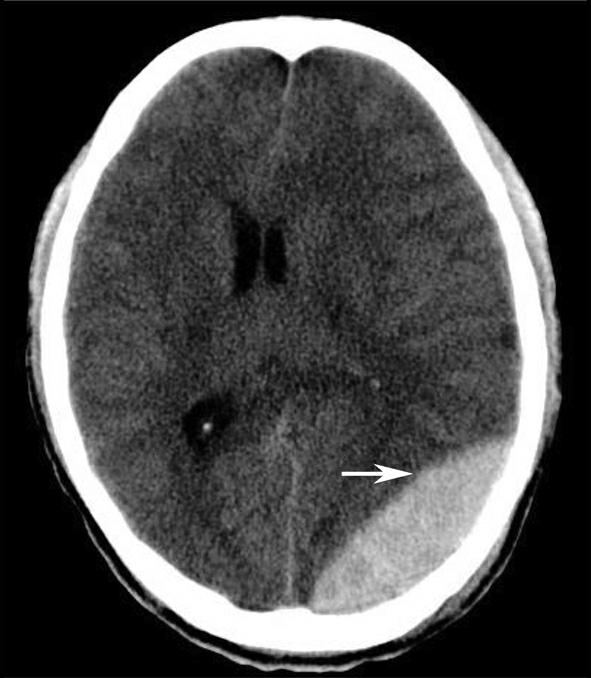

图1-2-20 环池闭塞

右侧颞叶脑内大血肿(★),产生严重的占位效应,环池受压闭塞(箭),脑疝形成